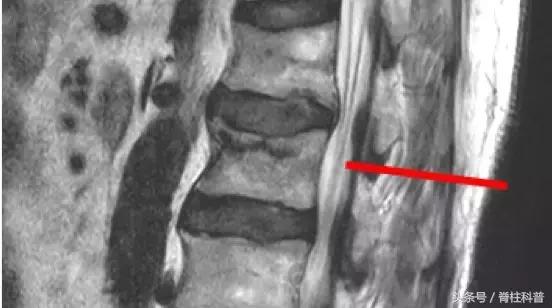

腰腿痛部分相关疾病图示

马尾综合症患者资料

脊柱结核